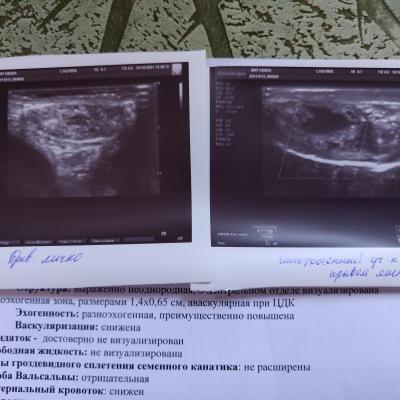

Прикрепляю УЗИ с фото образования, по нему нашли включение без кровотока. Насколько вероятно это опухоль? Достаточно ли сдать онкомаркеры АФП, ХГЧ и ЛДГ? Для исключения опухоли. Что такое микрокальцинаты? Опасны ли они в здоровом яичке?

Какая дальнейшая тактика обследования и прогноз? Смертельно ли это опасно, может ли мужчина быть полноценным? Большое спасибо за ответы. Вопрос задаю, потому что не могу найти себе места уже. Есть ли вероятность, что это не рак?! (УЗИ прикрепила недавнее с доплером с фото и старое УЗИ прошлого года, но оно мало информативное без доплерографии).